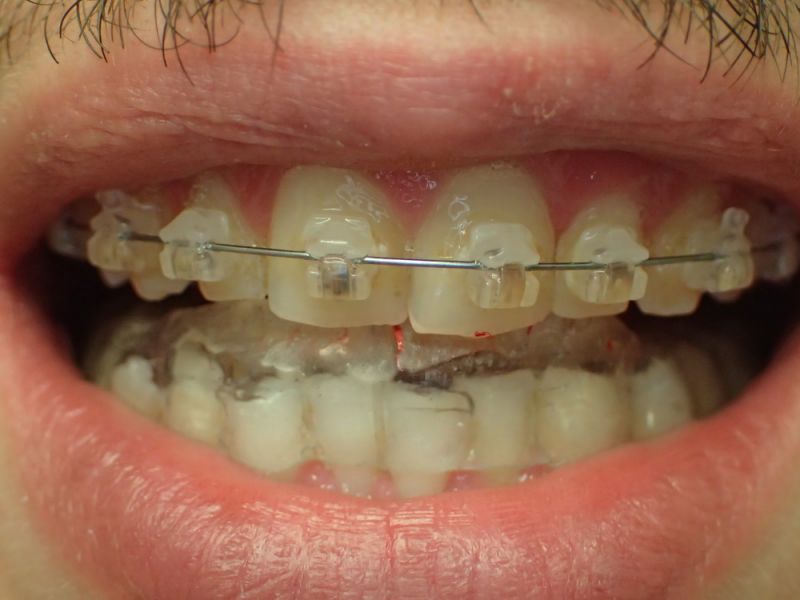

Daraufhin hat der Patient eine Kieferorthopädin konsultiert, die sich nach eigener Einschäötzung auf das Thema CMD spezialisiert hat. Ohne Vordiagnostik hat daraufhin eine Kieferorthopädische Erwachsenenbehandlung begonnen, die mit einer Bebänderung des Oberkiefers begann und nach kurzer Zeit zu geradezu explosionsartig verstärkten Bescherden des Patienten führte. Darauf angesprochen erklärte die konsultierte Kieferorthopädin, nach inzwischen 6000,-€ Behandlungskosten sie wisse nicht mehr weiter und könne dem Patienten nicht helfen.

Ohne in der Sache zu viel sagen zu wollen, kann man zumindest anmerken, dass es fragwürdig war einen Patienten, mit bereits bestehenden starken funktionellen Beschwerden kieferorthopädisch zu behandeln.

Es erfolgt dieErstuntersuchung und die Herstellung und Eingliederung eines adjustierten Aufbissbehelfs zum Nachweis einer CMD.